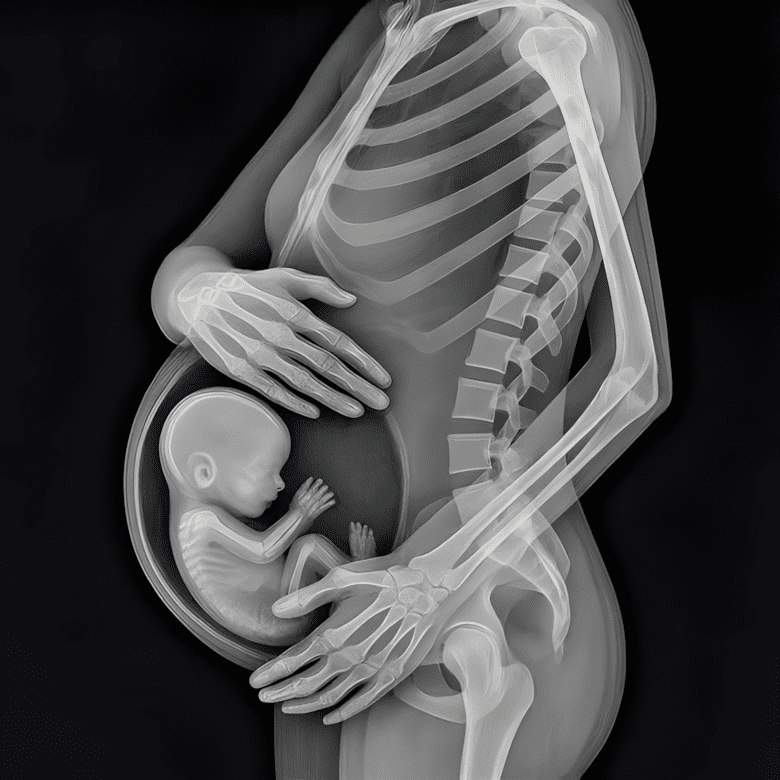

Weinig beelden vangen de realiteit van het moederschap zo indringend als de röntgenfoto van een zwangere vrouw: een fragiel skelet dat de kleine vorm van een baby omarmt, handen zachtjes om de zwellende buik gewikkeld in een gebaar van liefde en bescherming. Het is niet zomaar een medisch beeld – het is een symbool van opoffering, van kracht, van de verborgen strijd die elke moeder moet leveren.